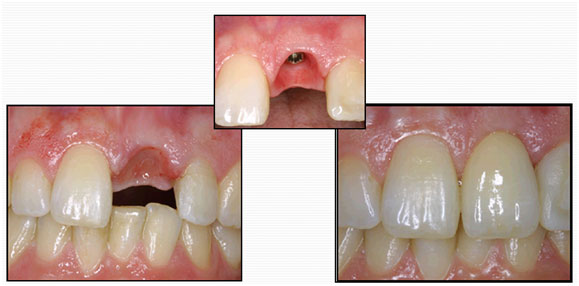

Only the missing tooth is treated. The adjacent teeth are not touched.

The success rate of a dental implant is incredibly high. It is placed under local anaesthesia by our implant surgeons, and is then allowed to heal and integrate with the bone.

Once healed, it is then restored with a crown.

Dental implants are the ideal solution for replacing missing teeth.

They significantly improve quality of life by enhancing your confidence, comfort and peace of mind.